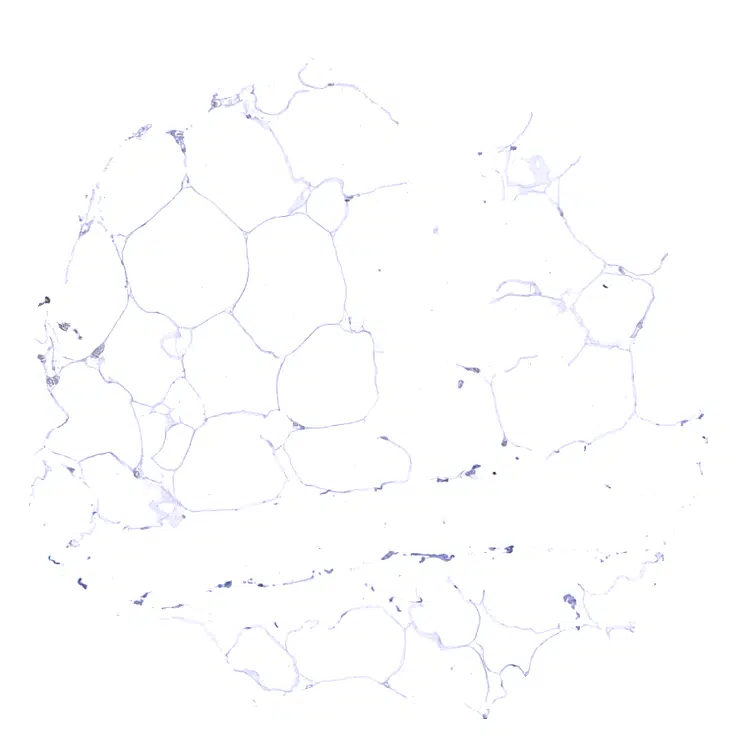

Fat